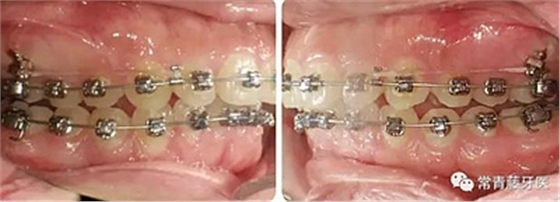

治療8個(gè)月,換0.018*0.025"CuNiTi弓絲,植入支抗釘,植入位點(diǎn)為上頜第一磨牙根上方顴牙槽嵴處,使其與牙根平行。同時(shí)嘗試性牽引遠(yuǎn)移上牙列。

治療12個(gè)月,更換為0.018*0.025”不銹鋼方絲,鎳鈦螺旋彈簧牽引內(nèi)收上牙列,同時(shí)下頜配合Ⅱ類牽引。

治療15-22個(gè)月,弓絲打搖椅,進(jìn)一步控根內(nèi)收。

治療23個(gè)月結(jié)束。可見兩側(cè)尖磨牙達(dá)到中性關(guān)系,上下牙列排齊整平,前牙覆合覆蓋正常,中線齊。